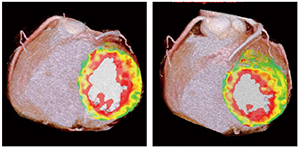

61歳,男性。ステント留置後の経過観察のため心臓CT検査を施行した。現在無症状であるが,負荷Dynamic CTPでは下壁に血流異常を認めた。遅延造影CTでは血流低下領域に一致した心筋遅延造影が認められ,心筋梗塞を見ていることが判明した(図4)。本症例は,ステント留置領域における内膜下梗塞と,ステント再狭窄に起因する心筋虚血の鑑別に,遅延造影CTが重要な役割を果たすことを示している。

図4 症例2:Voxel-wise MBF mapと遅延造影CT(CTDE)